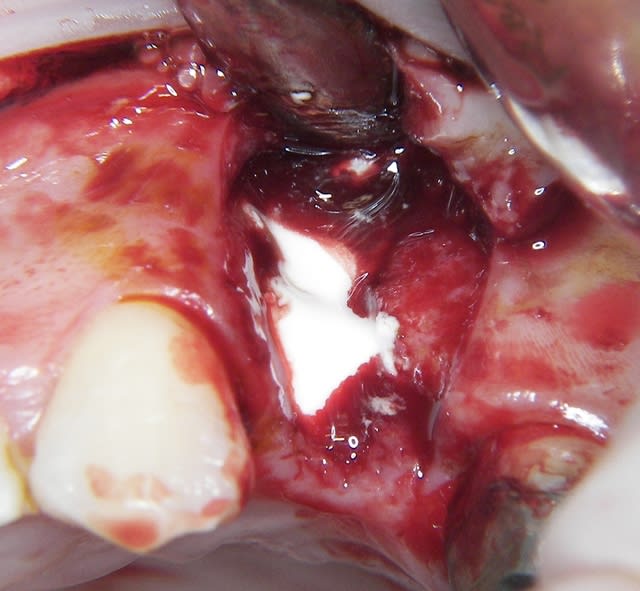

un exemple ce matin

j'en ai un autre cette AM mais probleme de carte sim

j'adore ce produit seul imperatif bien respecter le mode d'emploi